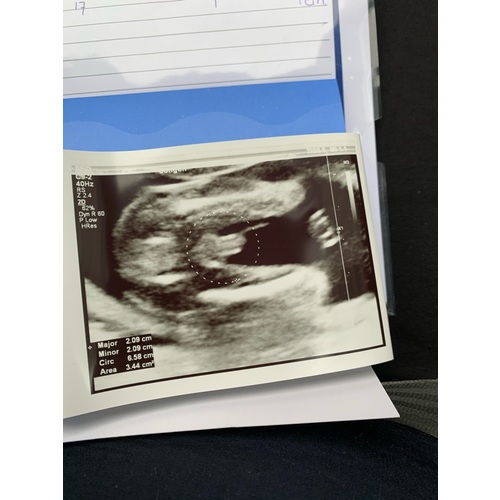

Lijkt mij wel echt een jongen! Ben geen ervaringsdeskundige natuurlijk, maar lijkt redelijk op hoe onze geslachtsecho was 😏

Lijkt inderdaad op een jongen. Zie onze echo wij krijgen ook een jongen. Die van ons is wel stuk duidelijk vindt ik zelf. Bij een meisje zie je een streepje en geen uitsteeksels

Duidelijk een jongen. Ik krijg een meisje en daarbij zag je duidelijk de hamburger, hier zie je echt balletjes.